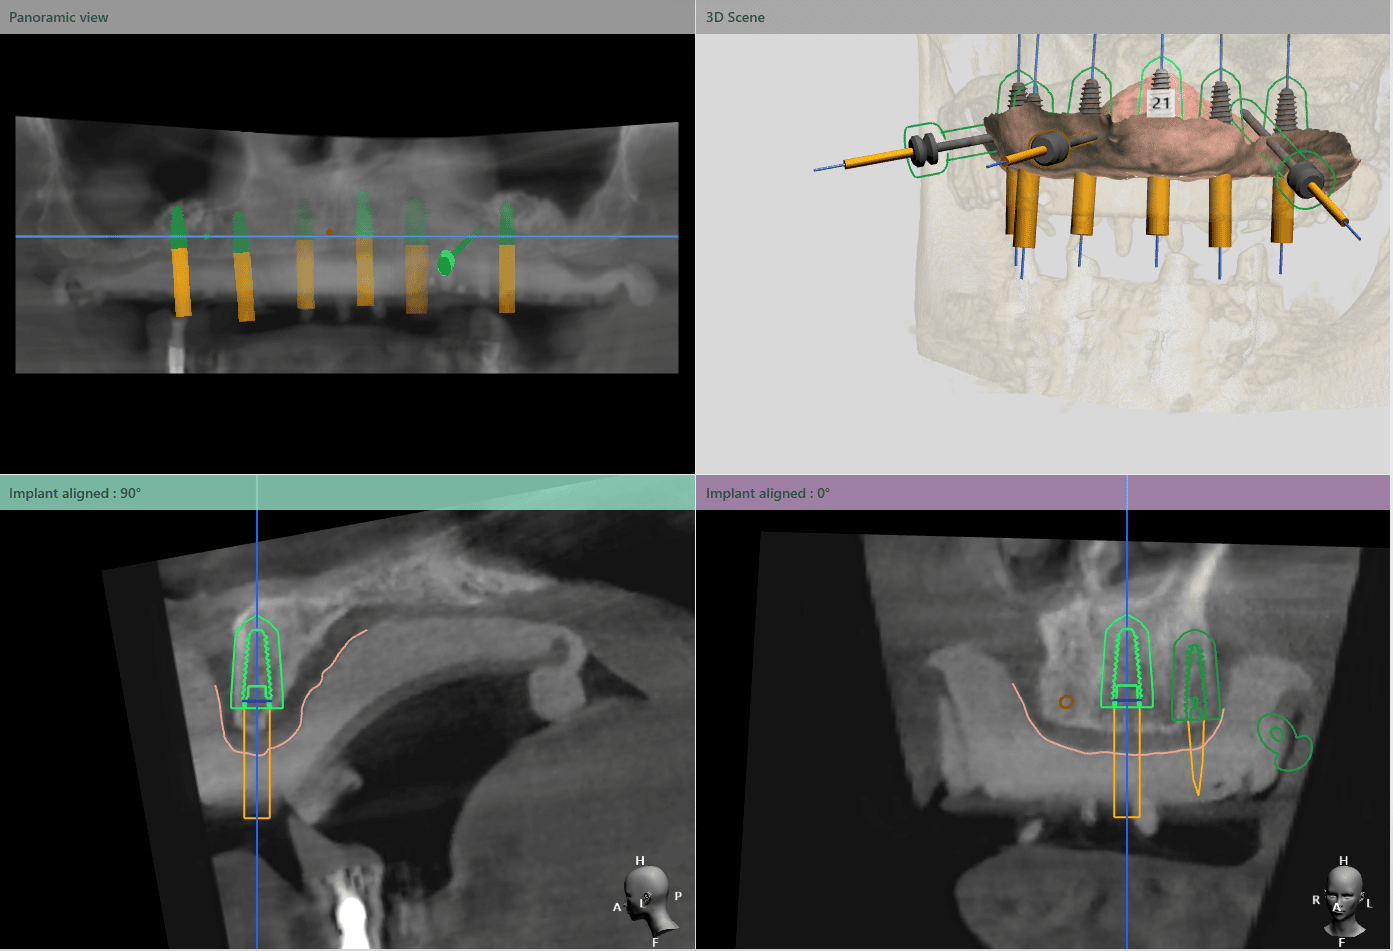

Medicul specialist a efactuat scanarea digitală a arcadelor pe care a trimis-o tehnicianului dentar DigiRay, împreună cu CBCT-ul pacientului.

Odată planficată și agreată poziția și axul de inserție al fiecarui implant, tehnicianul DigiRay efectuează designul șablonului chirurgical și printarea acestuia dintr-o rășină bio-compatibilă.

Ulterior, tehnicianul editează protocolul și secvența de frezare conform sistemului de implanturi și trusei chirurgicale folosite de către medic și îl trimite prin email medicului curant.